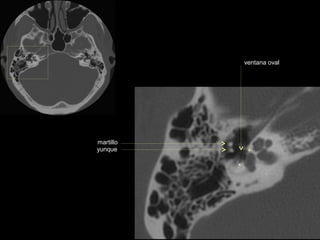

ventana oval

martillo

yunque

cóclea